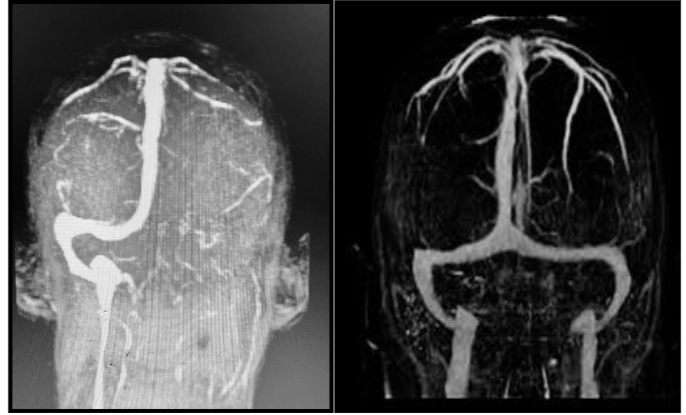

Pre-procedural CT venography revealed extensive thrombosis of the superior sagittal sinus, characterized by a lack of opacification in the affected sinus, indicating complete occlusion. Post-procedure, cerebral venous flow was successfully restored, and follow-up imaging confirmed patency of the venous sinuses.